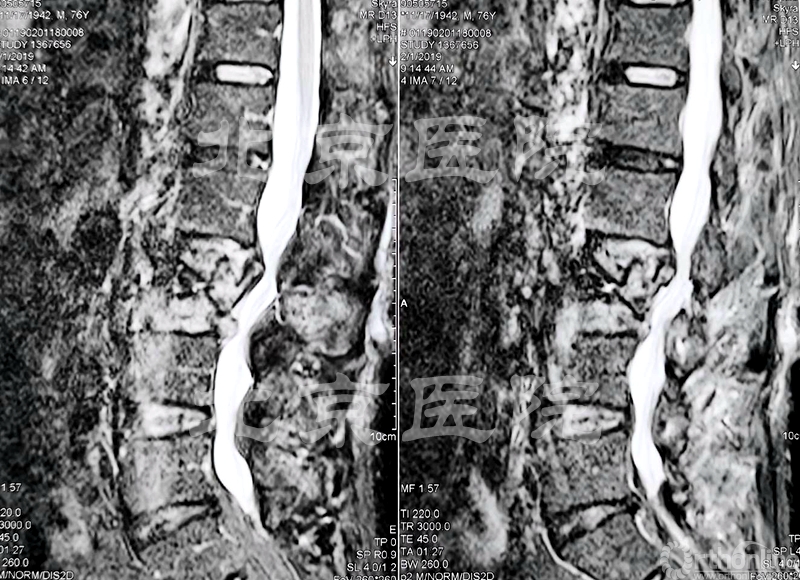

术前影像检查

患者为76岁男性,腰痛多年加重一月伴有腿疼,多年前曾有腰部外伤史,由于资料缺失原因不详。患者患有类风湿关节炎多年,需要常年使用激素治疗;伴有腰椎间盘突出症病史20多年,偶尔发作,合并有重度骨质疏松症;腰部BMD:-3.9(0.162g/cm2).

经检查发现患者脊柱外观无侧弯,腰部平直微向后凸,L2-L4椎体压叩痛阳性;腰椎前屈40度、左侧弯20度、右侧弯20度;双侧支腿抬高试验阴性,双下肢肌力、感觉及反射正常,双侧股神经牵拉试验阳性;双侧病理征未引出,双侧髋关节4字试验阴性。